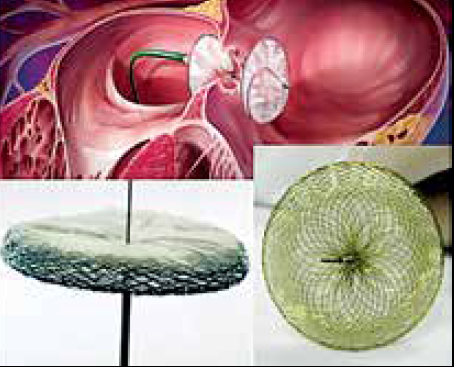

Como é feito o procedimento por cateter?

O cateter oclui os vasos sanguíneos que nutrem o excesso de músculo responsável pelo problema.

Sem nutrição, o excesso de músculo definha e não mais obstrui a saída do coração.

A substância que oclui a artéria nutridora do excesso de músculo é um copolímero, ou álcool.

Copolímero parece ser mais seguro que o álcool.